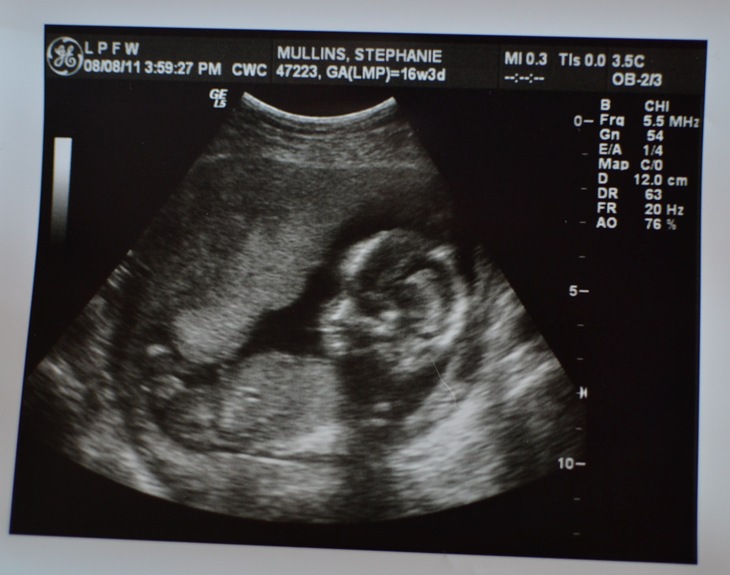

*Finding out what the fifth and final member of the Mullins family is - I went in for a check-up with a new doctor a little over a week ago when I was right at 16 weeks, and they decided to do an ultrasound to do measurements and check on everything. I was told that they might be able to tell what the gender was, so I took the girls with me. My mom had planned on going since Joe was at work, but he got off early, so he came instead. The doctor was running really behind because he had to go deliver some babies, so we were waiting for around 3 hours. They finally got me back to the ultrasound room and the tech said, “It might be too early to tell what it is,” as she was looking around the screen. I was so anxious… I’d been dying to know what we were having, as had Joe and everyone else we know. I offered to do jumping jacks to move things around a bit, but it wasn’t necessary, because a few minutes later, she said, “That might just be a penis!” My heart jumped. I’m not going to lie… if it had been another girl, we would have been disappointed for a few minutes. I could see the astonishment and happiness on Joe’s face. I looked at the nurse, and said, “Are you 100% sure?” I wasn’t expecting her to say yes, but she did. “100%”

We were dying to tell everyone, but wanted our parents to hear it first. Joe’s dad lives kind of far out of town, so he went ahead and texted him a picture or the sonogram. His response? “Good job, I was starting to wonder if you had it in you.”